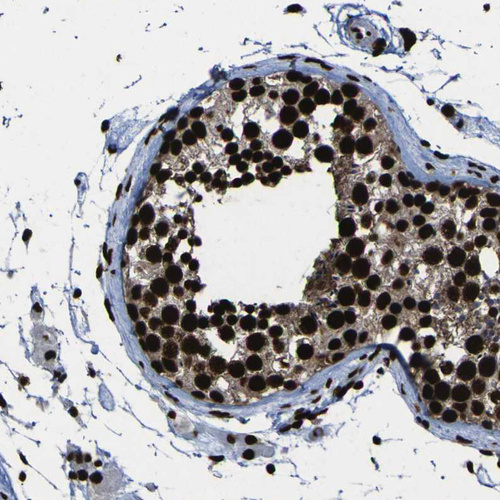

Immunohistochemical staining of human endometrium shows moderate to strong nuclear positivity in glandular cells.